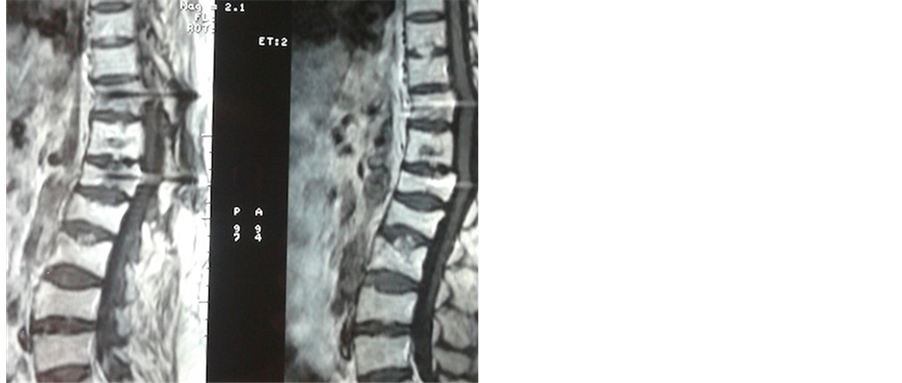

Patient was treated successfully for 6 months by ethanol embolization, with posterior decompression (lamin- ectomy and fixation), followed by radiotherapy sessions. After the 6 months of treatment, Thoraco-Lumbar MRI didn’t found canal extension signal (Figure 4). Pain, neurological also disappeared and the clinical examination did not objectified signs for neurological deficit.

Figure 4. Sagittal thoraco-lumbar spine MRI image after surgery showed soft spine canal and vertebral body. Vertebral fractures and intra-spongy hernias of L1-L2.